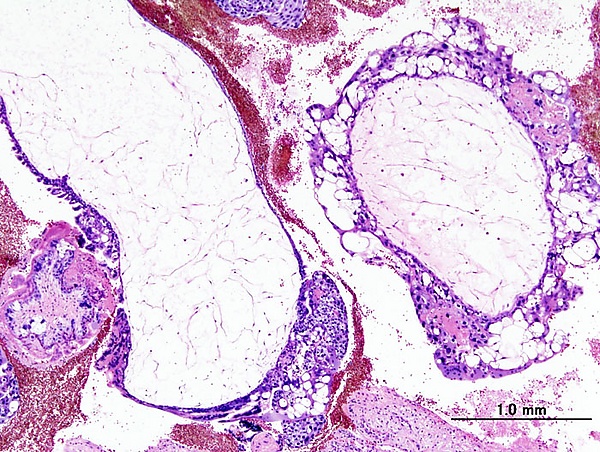

Пузырный занос бывает полным, при котором отсутствуют ткани эмбриона, и неполным, при котором эмбрион или его отдельные элементы присутствуют. Полный пузырный занос наблюдается вследствие оплодотворения дефектной яйцеклетки, не имеющей хромосом. В процессе дальнейшего деления отцовские хромосомы удваиваются, однако такая зигота является нежизнеспособной, так как эмбрион не образуется, и происходит только рост ворсин. Неполный пузырный занос образуется в связи с оплодотворением яйцеклетки двумя сперматозоидами, поэтому клетки в этом случае содержат большое количество дополнительных хромосом, что также делает продукт зачатия нежизнеспособным. Ткань пузырного заноса вырабатывает большое количество хорионического гонадотропина, который приводит к образованию в яичниках лютеиновых кист. В 15-20 % случаев пузырный занос трансформируется в хорионэпителиому — злокачественная опухоль, то есть внедряется в здоровые ткани и даёт метастазы.